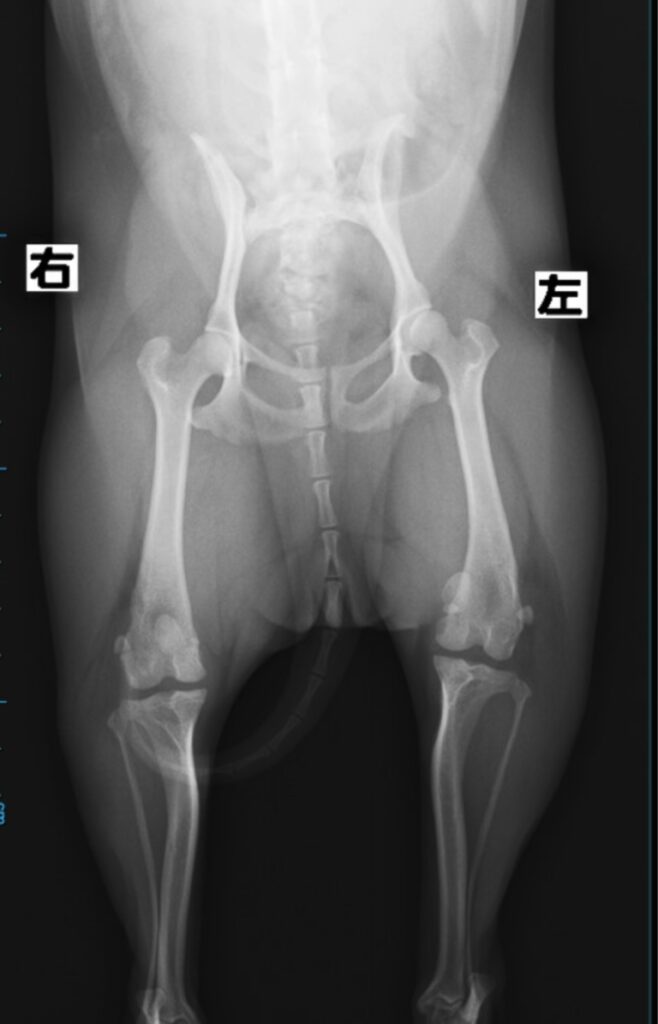

「チワワのMPLGrade3 Pre Xray」

「術中所見:大腿骨滑車部位の軟骨損傷、欠損」

この部位で膝蓋骨(パテラ)は容易に脱臼します。

この部位の脱臼を防ぐ為には滑車溝を形成(深く)しても脱臼してしまうでしょう。。